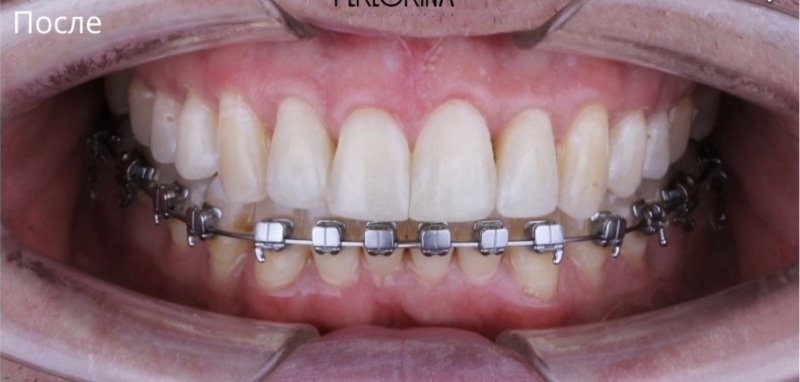

Установка металлических брекетов

Диагноз: 1. Смыкание справа по дистальному типу; 2. Трансверзальная резцовая окклюзия; 3. Глубокая резцовая окклюзия; 4. Тремы верхнего зубного ряда; 5. Смещение нижних резцов вправо; 6. Супраположение 1.3. Для лечения использована Металлическая лигатурная брекет-система. Срок ношения 1,5 года. В результате лечения мы получили: 1. Нормализацию смыкания в боковых отелов; 2. Нормализация косметического центра; 3. Добились правильного резцового перекрытия; 4. Устранили сужение зубных рядов.

Доктор: Хачатрян Лариса Рубеновна